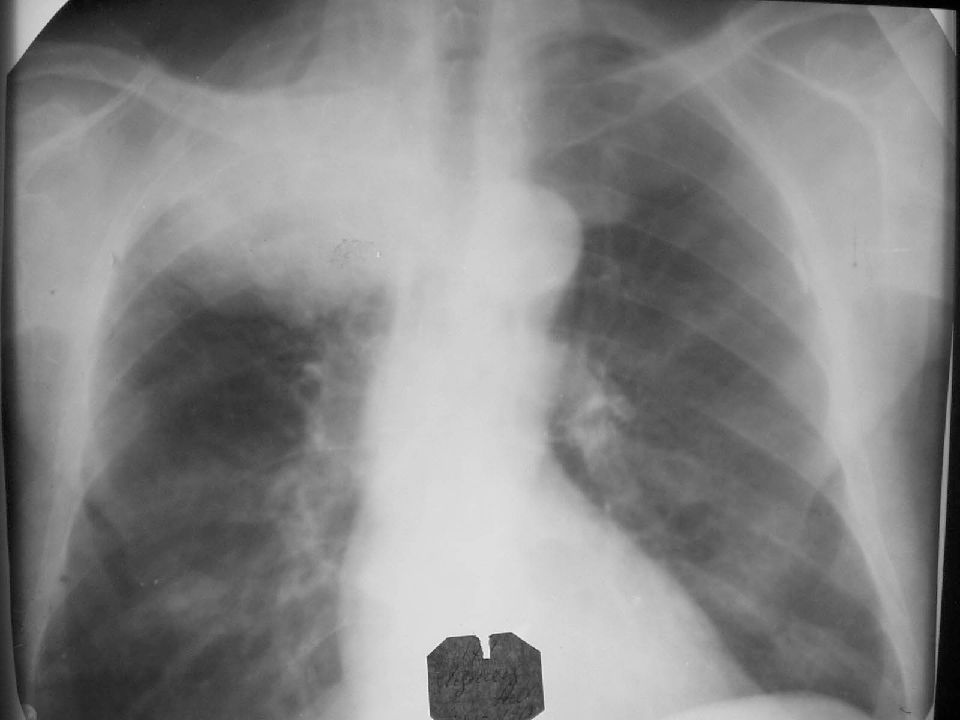

Рентгенологические изображения и синдромы патологии легких

Раздел: Кадры-подсказки